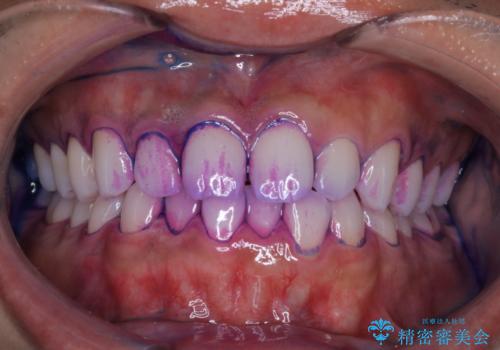

ぱっと見しっかり磨けているように見えますが、染だしをしてみると歯ぐきの境目などに磨き残しがあることがわかります。定期的に染め出しを行い、日々のブラッシングの癖や磨き残しを把握することで、改善するべきポイントが明確に発見されます。